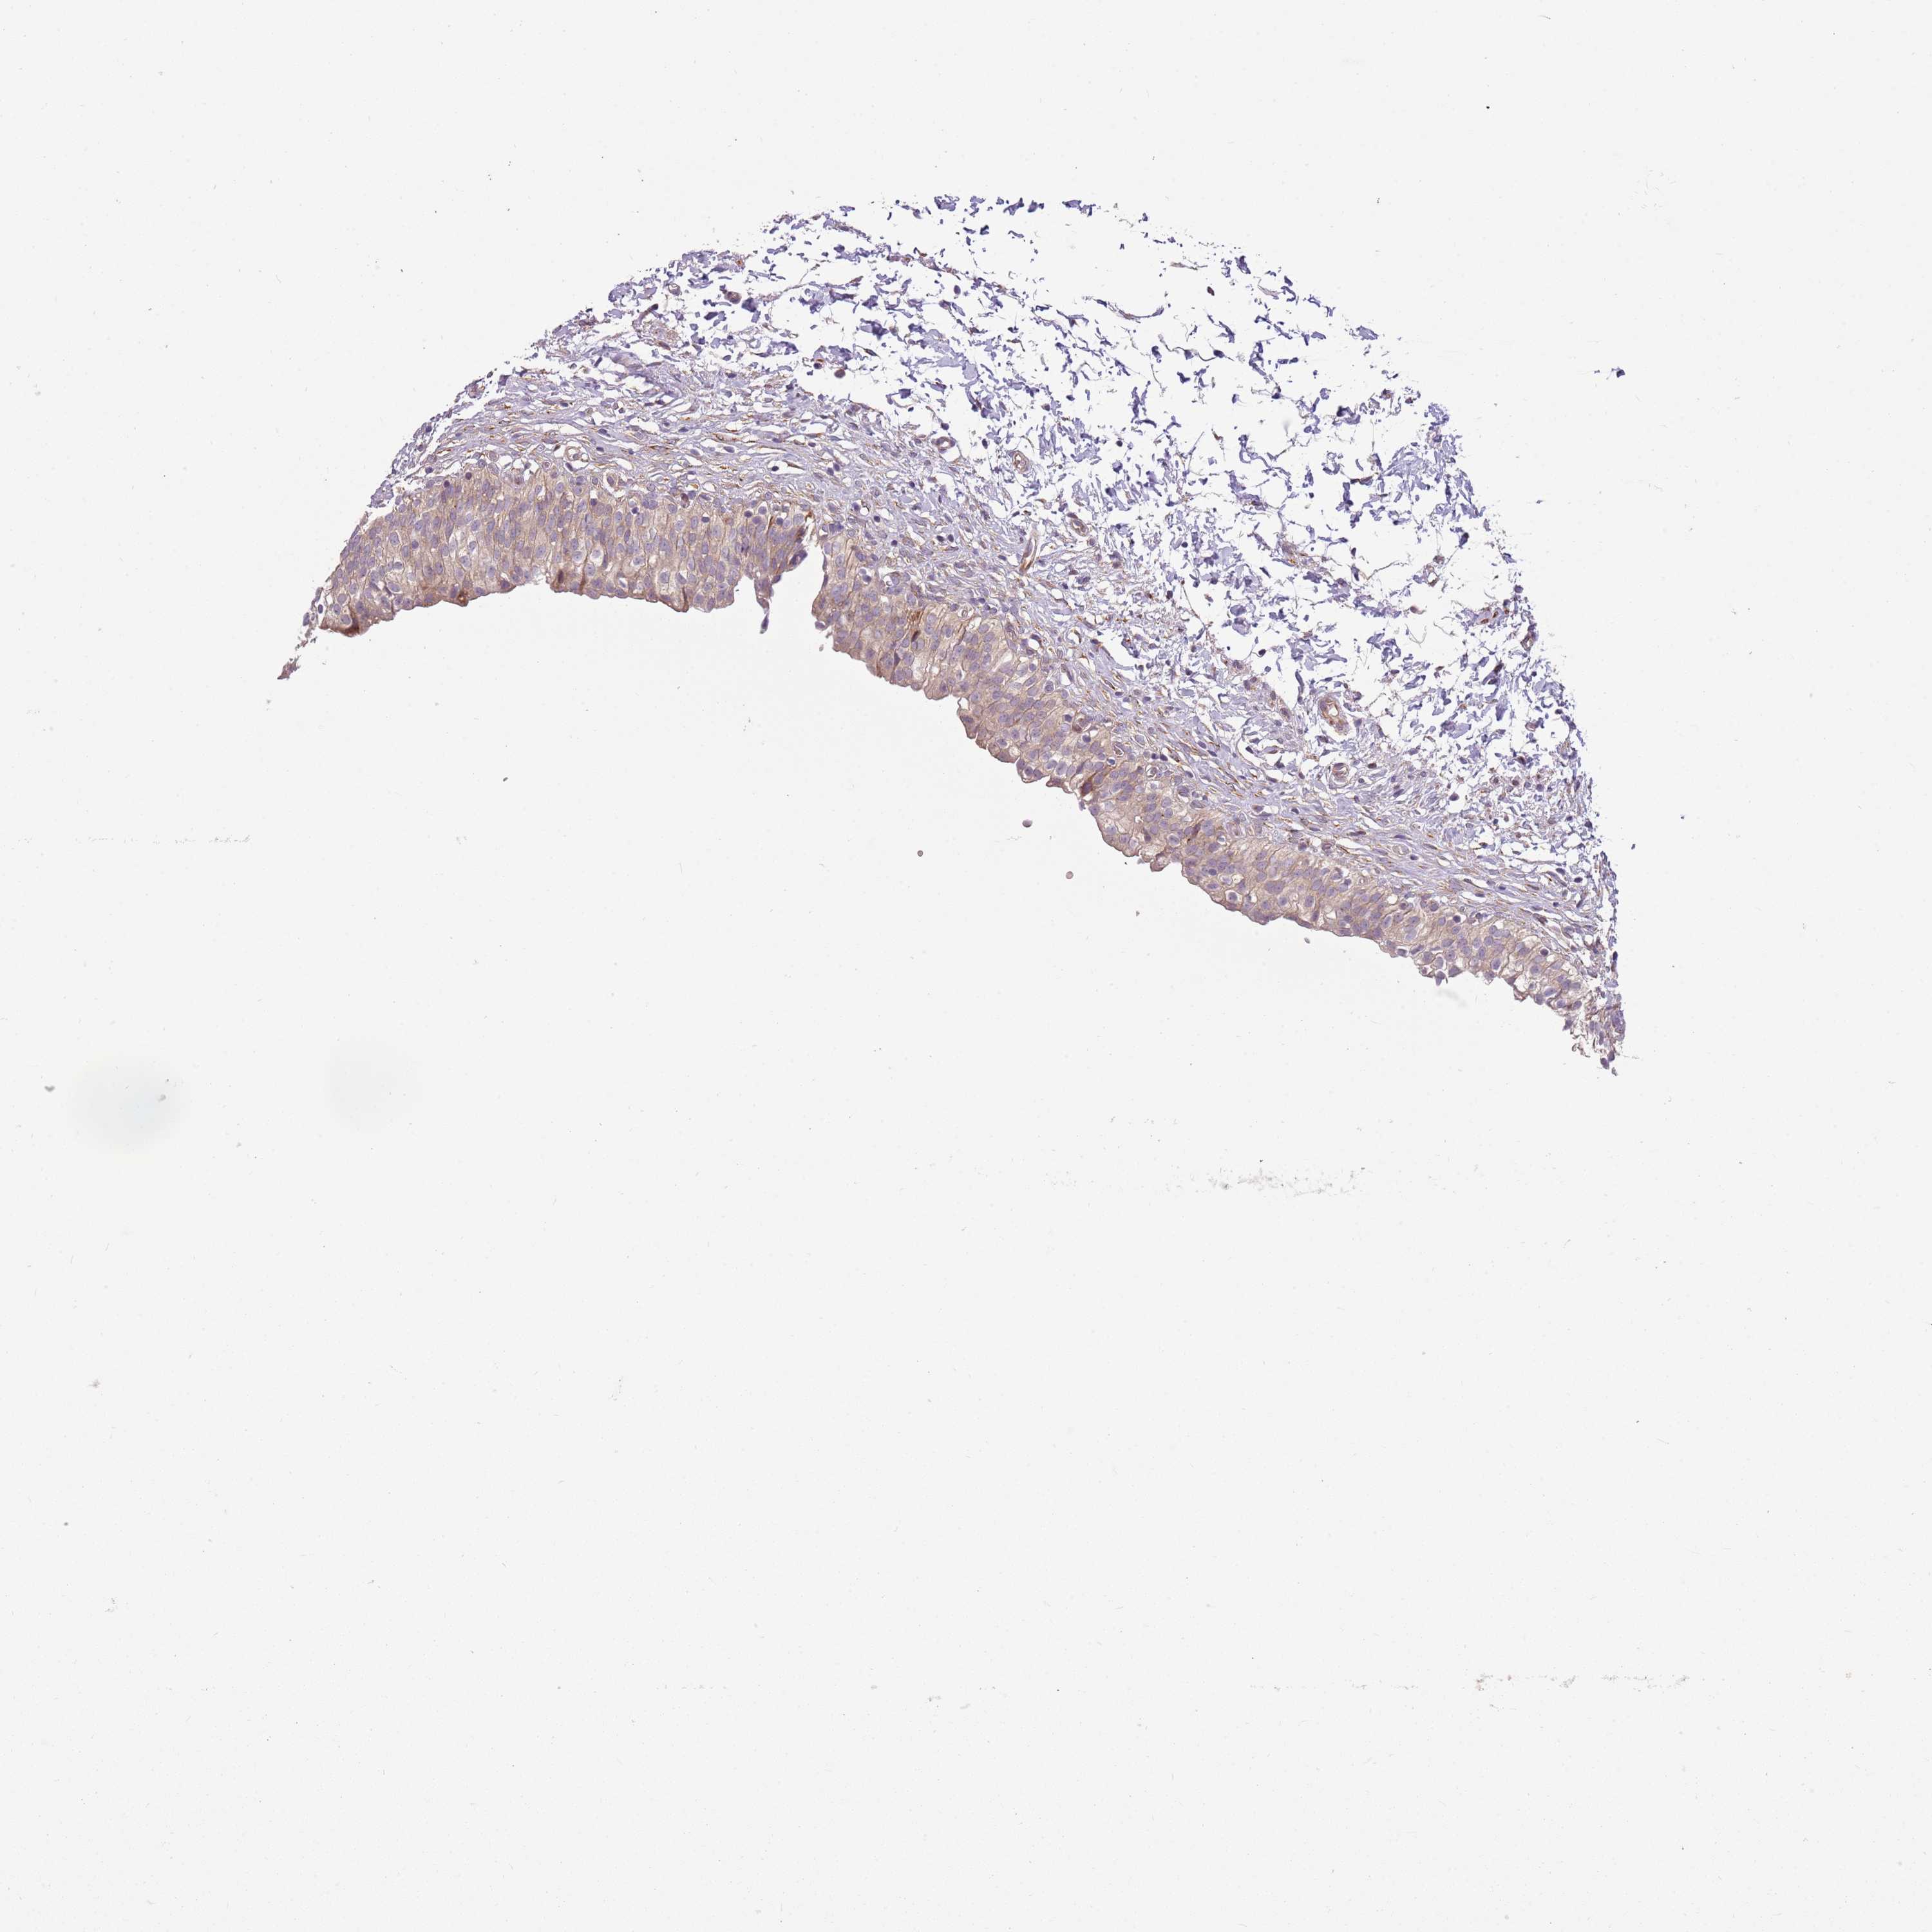

URINARY BLADDER - Antibody stainingi

Antibody staining in the annotated cell types in the current human tissue is reported as not detected, low, medium, or high, based on conventional immunohistochemistry profiling in selected tissues. This score is based on the combination of the staining intensity and fraction of stained cells. Each image is clickable and will lead to virtual microscopy that enables deeper exploration of all samples and also displays staining intensity scores, fraction scores and subcellular localization as well as patient and tissue information for each sample.

Antibody HPA047497

Urothelial cells High